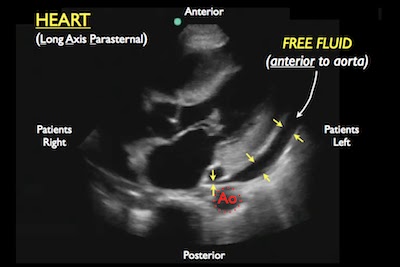

- Component: Heart (parasternal long axis view)

- Finding: Pericardial effusion (tamponade)

- Small effusions are best identified posterior to left ventricle (dependent portion of pericardium)

- Can find compression of the right ventricle (Singh S et al Sens 92%, Spec 100%, PPV 100%)